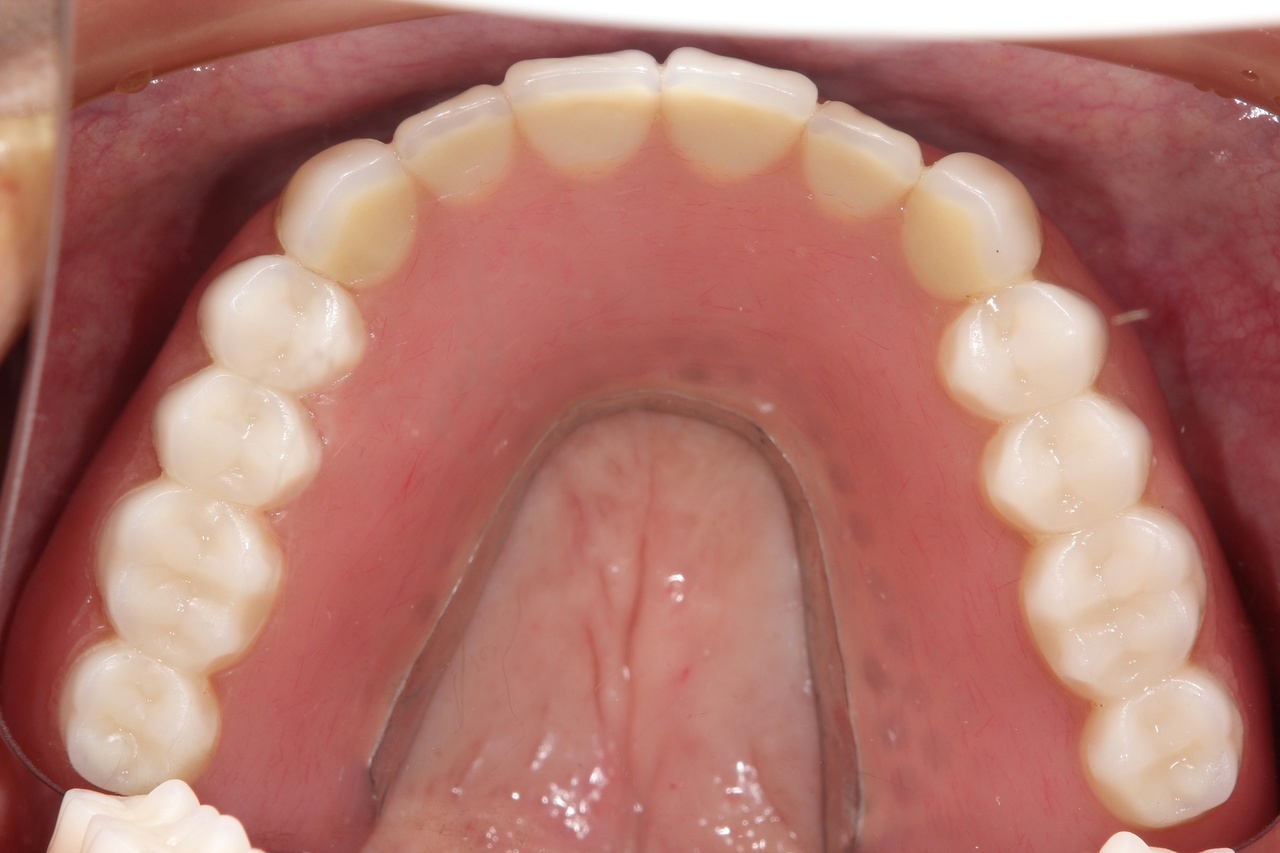

歯周病とインプラント(抜歯即時荷重)<ガイドシステムを使用した埋入法>

インプラント8本で14本の歯を並べたケース・仮歯代含む (函南町在住 女性

抜歯後、片顎8本のインプラントを埋入し、即日に仮歯を製作する事により、1日で片顎14本の歯を回復します。事前にインプラントを埋入する位置をCTによりシミュレーションし、埋入ガイド、仮歯を準備したうえで手術を行います。埋入ガイドにより、正確な位置にインプラントを埋入することができます。

仮歯装着①

インプラント埋入後、その日に用意していた仮歯を装着します。

仮歯装着②

仮歯をネジ止めして固定します。

これはまだネジ穴を塞いでいない状態です。

最終的な被せ物装着

インプラントがしっかり骨に定着したら、型取りをして、最終的な被せ物を製作し、装着します。

【下顎インプラント8本で14本の歯を回復するスクリュー固定タイプ】

インプラント手術:250,000円×8本=2,000,000円

静脈内鎮静法:0円

既製アバットメント:90,000円×8個=720,000円

メタルボンド:130,000円×14本=1,820,000円

マルチアバットメント:25,000円×8個=200,000円

連結料:10,000円×13カ所=130,000円

仮歯:50,000円×8本=400,000円

ポンティック:10,000円×6本=60,000円

ラジオグラフィックガイド(11本):22,000円

埋入ガイド(8本):73,000円

総額:5,425,000円+税